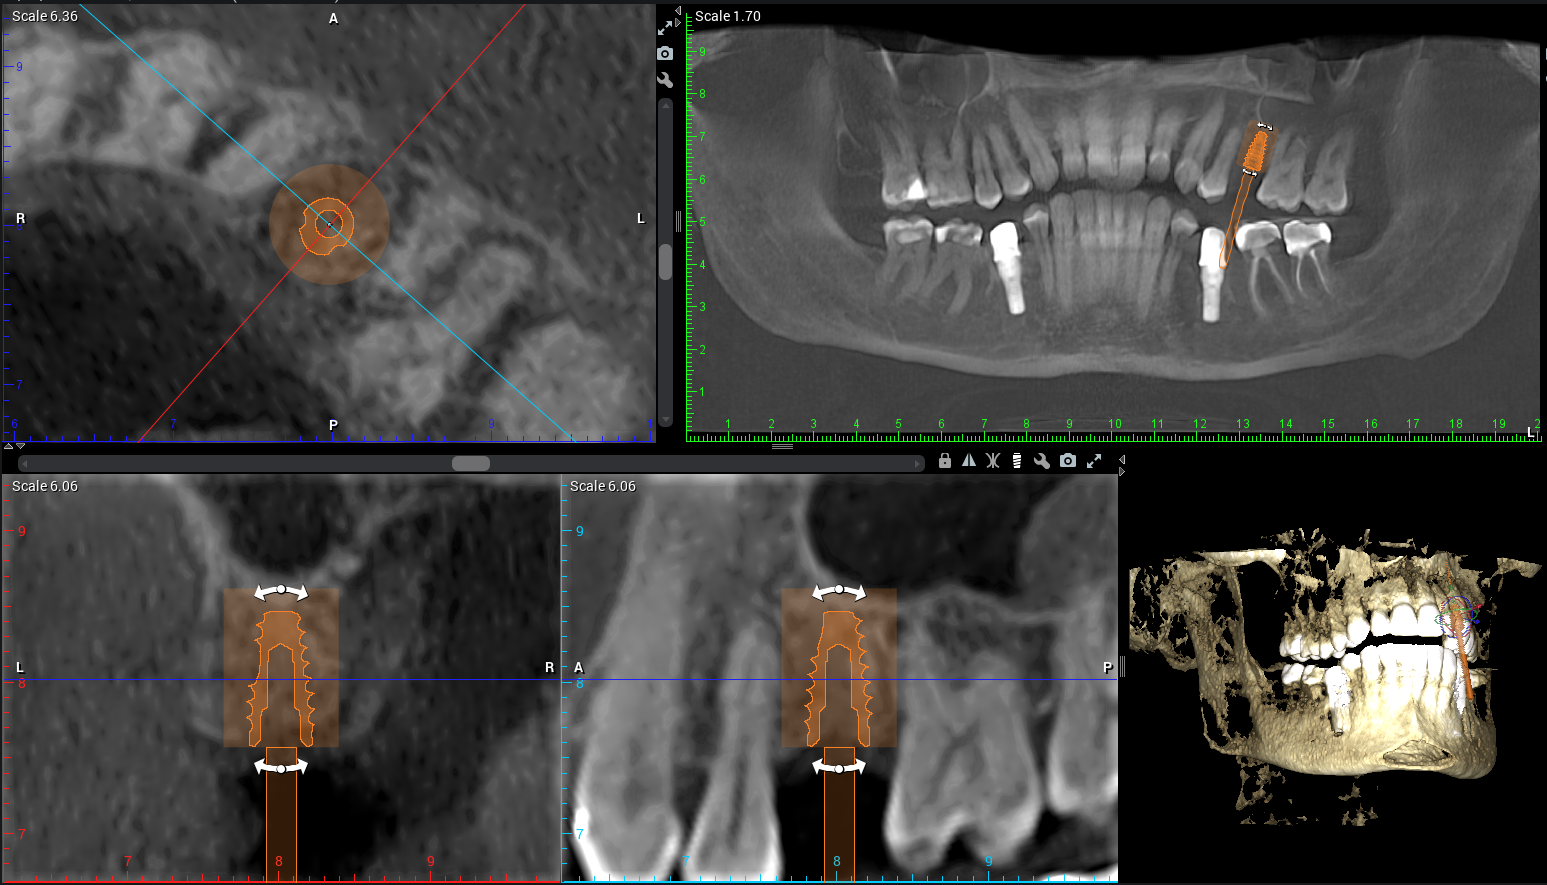

At Teuscher Legacy Dental, every implant case is planned with 3D cone beam CT imaging and digitally designed surgical guides — the same technology used by other leading surgical centers.

Visualize bone quality, and sinus anatomy, and nerve locations

Place implants with extreme precision

Often shorten healing time and improve comfort

Optimize location of future crown (the chewing part of the implant)

This first step also helps make sure the patient is on the same page with what to expect a final result to look like. We also go over financial details and timeline. This way the patient knows what to expect every step of the way!CBCT 3D Planning

CBCT (3‑D imaging) is used to assess bone quantity and quality and check for any sinus or nerve issues. There should be an evaluation of overall health (e.g., diabetes, smoking, medications) and other risk factors. Gum health should also be assessed (are there active gum infections?) and whether bone grafting is needed.Use of guided surgical planning

Digital planning and surgical guides help dentists place implants at the right angle, depth, and position, avoid critical anatomy (sinus, nerves), and preserve bone and soft tissue.Strict surgical protocol and sterile technique

Why it matters: The foundation of a successful implant starts with precision planning. During your consultation, our doctors use a cone-beam CT (CBCT) scan to create a 3D model of your teeth, bone, and jaw structure.

CBCT imaging allows us to measure bone density, identify vital structures (like nerves and sinuses), and plan the exact position of your future implant.

Using digital treatment planning, we design a custom surgical guide to ensure the implant is placed with millimeter accuracy.

Example of Teuscher Legacy Dental’s 3D implant Planning Software

3D scans (CBCT imaging) and digital planning lead to better fit, healing, and long-term success. A 2D X-Ray is less expensive, but also doesn’t allow for the same precision in planning where the implant post will sit in your jawbone. Sometimes, a dentist will use the 3D scan to generate a surgical guide, which allows for even greater precision when surgically placing the post.